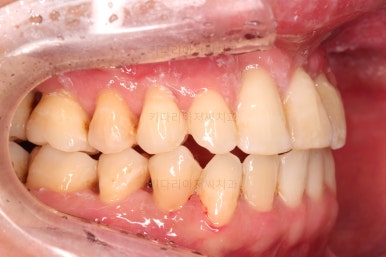

1. 초진 시 입안의 모습

부산구순구개열교정 키다리아저씨치과에 처음 내원하셨을 당시의 입안의 모습입니다.

구순구개열 환자분의 일반적인 입 안의 특징은 다음과 같습니다.

골 결손부위의 치아 결손이 빈번하다.

구개열 봉합술을 어린 나아이에 받기 때문에, 해당 부위의 상흔이 남는다.

상흔의 영향으로(피부 상처도 일반 피부 보다는 상처가 아문 부위가 더 단단하죠.) 입천장의 잇몸이 굉장히 단단하다.

그래서 가로폭의 성장이 잘 되지 못하여 악궁(치아가 배열된 U자 형태)이 협착된 경우가 많다.

공간 부족으로 치열이 매우 삐뚠 경우가 많다.

공간 부족과 악궁 형태 등으로 인해 부정교합이 함께 나타난다.

골 결손부위 근처의 치아는 뼈가 약한 경우가 많아 튼튼하지 못하고 만지면 흔들리는 경우가 많다.

이번 환자분도 이와 같은 일반적인 특징이 그대로 나타나 있었습니다.

양측성 구순구개열이었으므로 작은 앞니(대문니와 송곳니 사이)가 양쪽 다 결손이었고, 또 다른 이유로 아래 앞니도 1개 없는 상태였습니다.